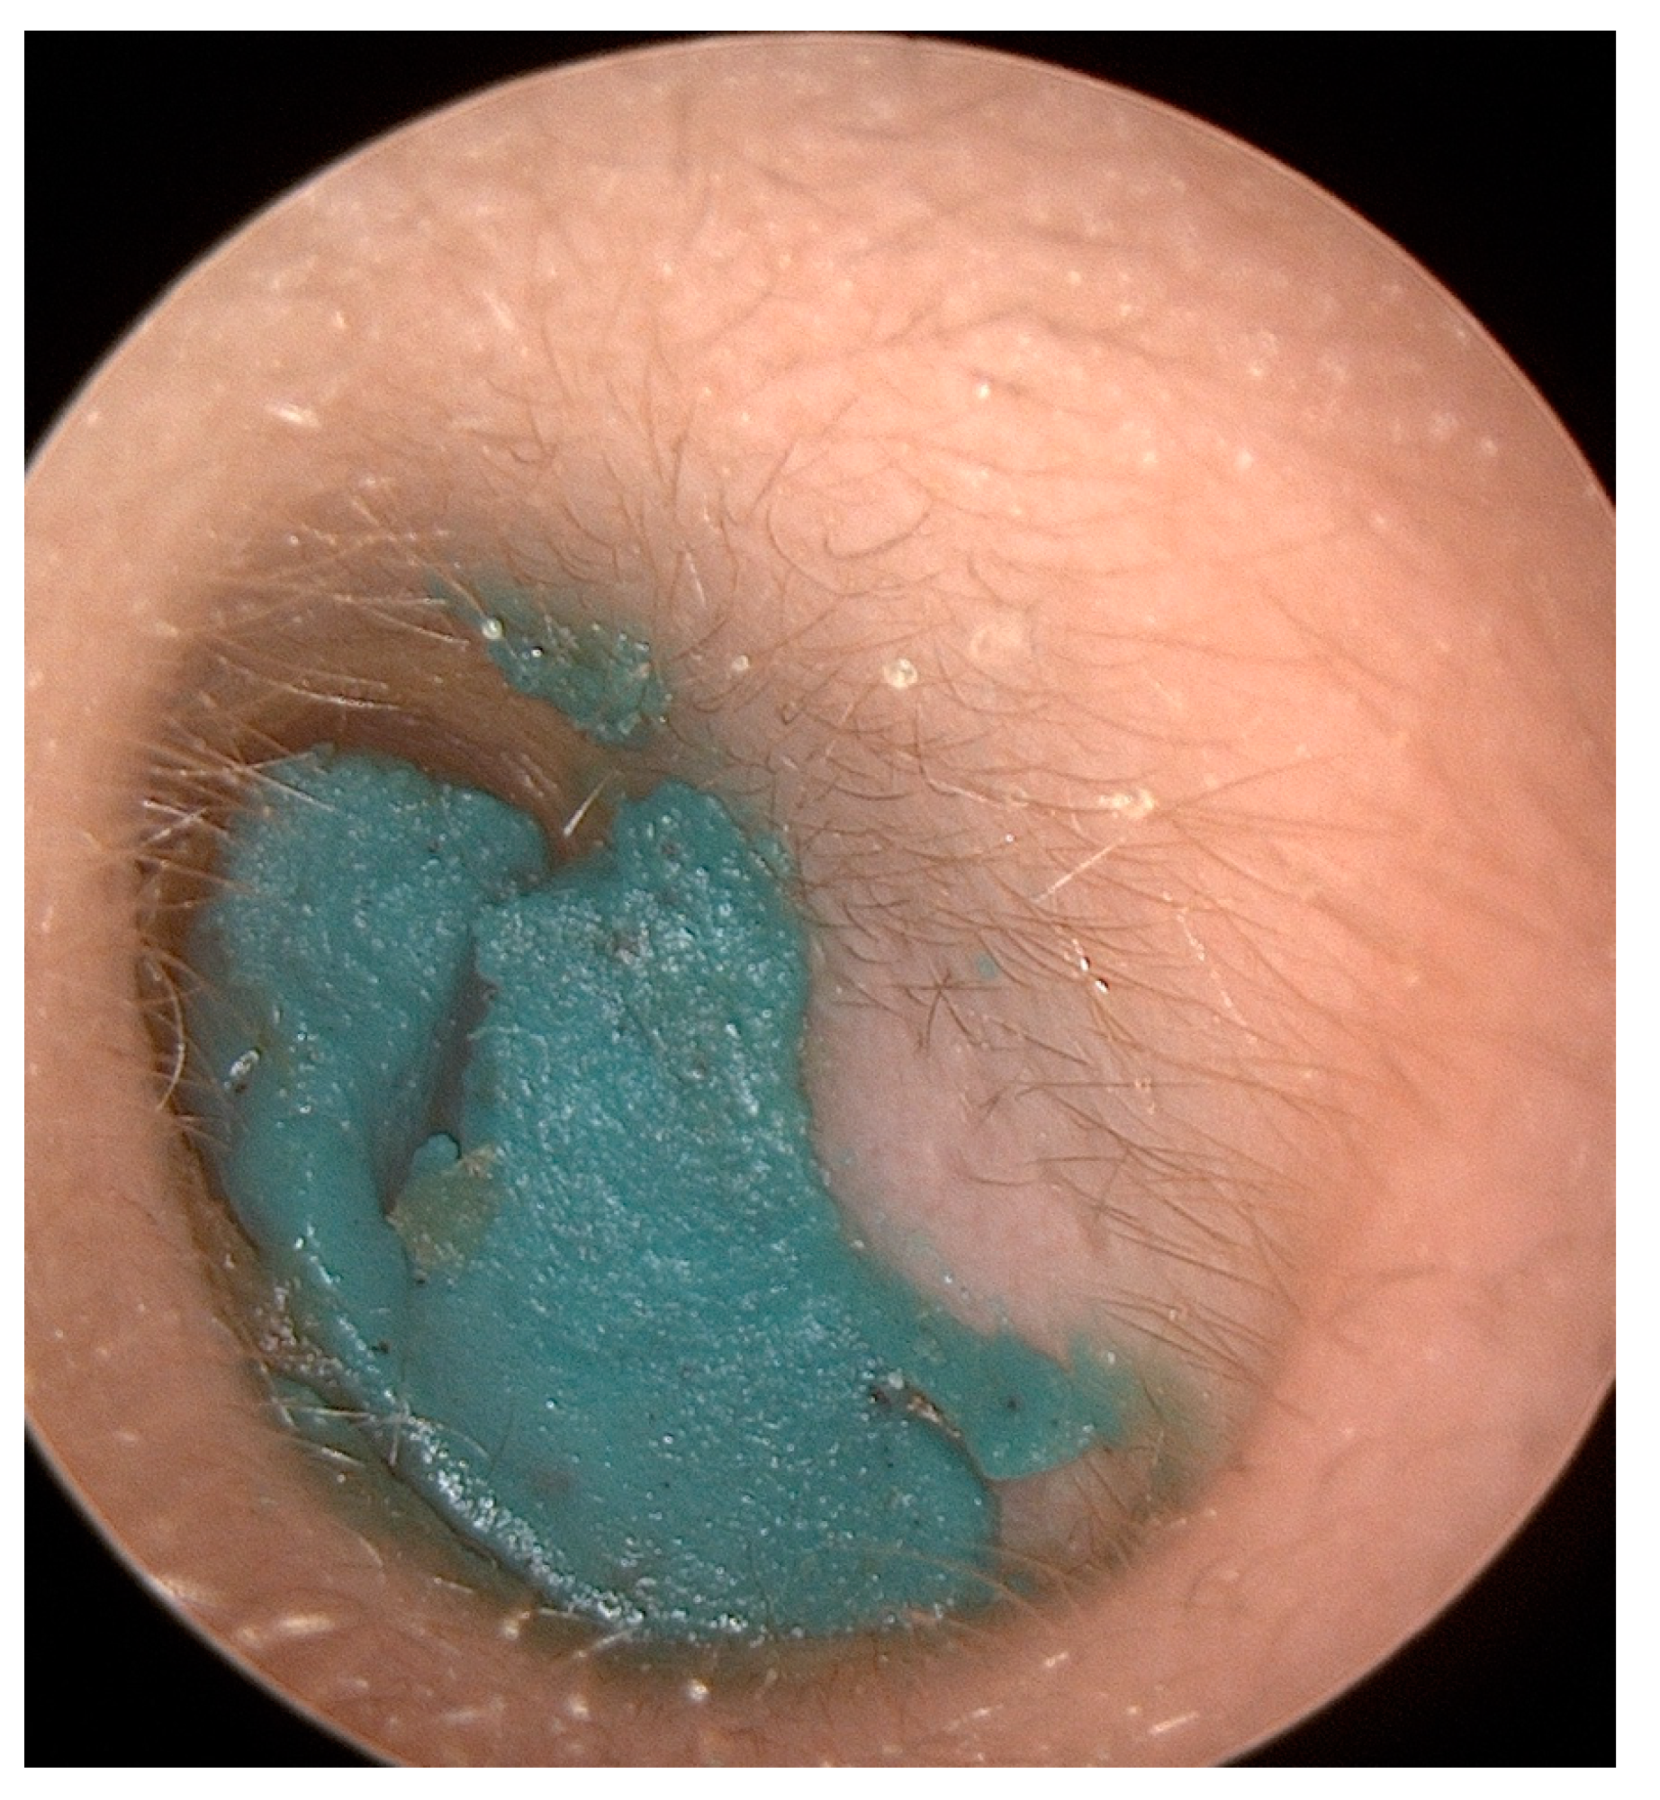

2. Aural Foreign Bodies